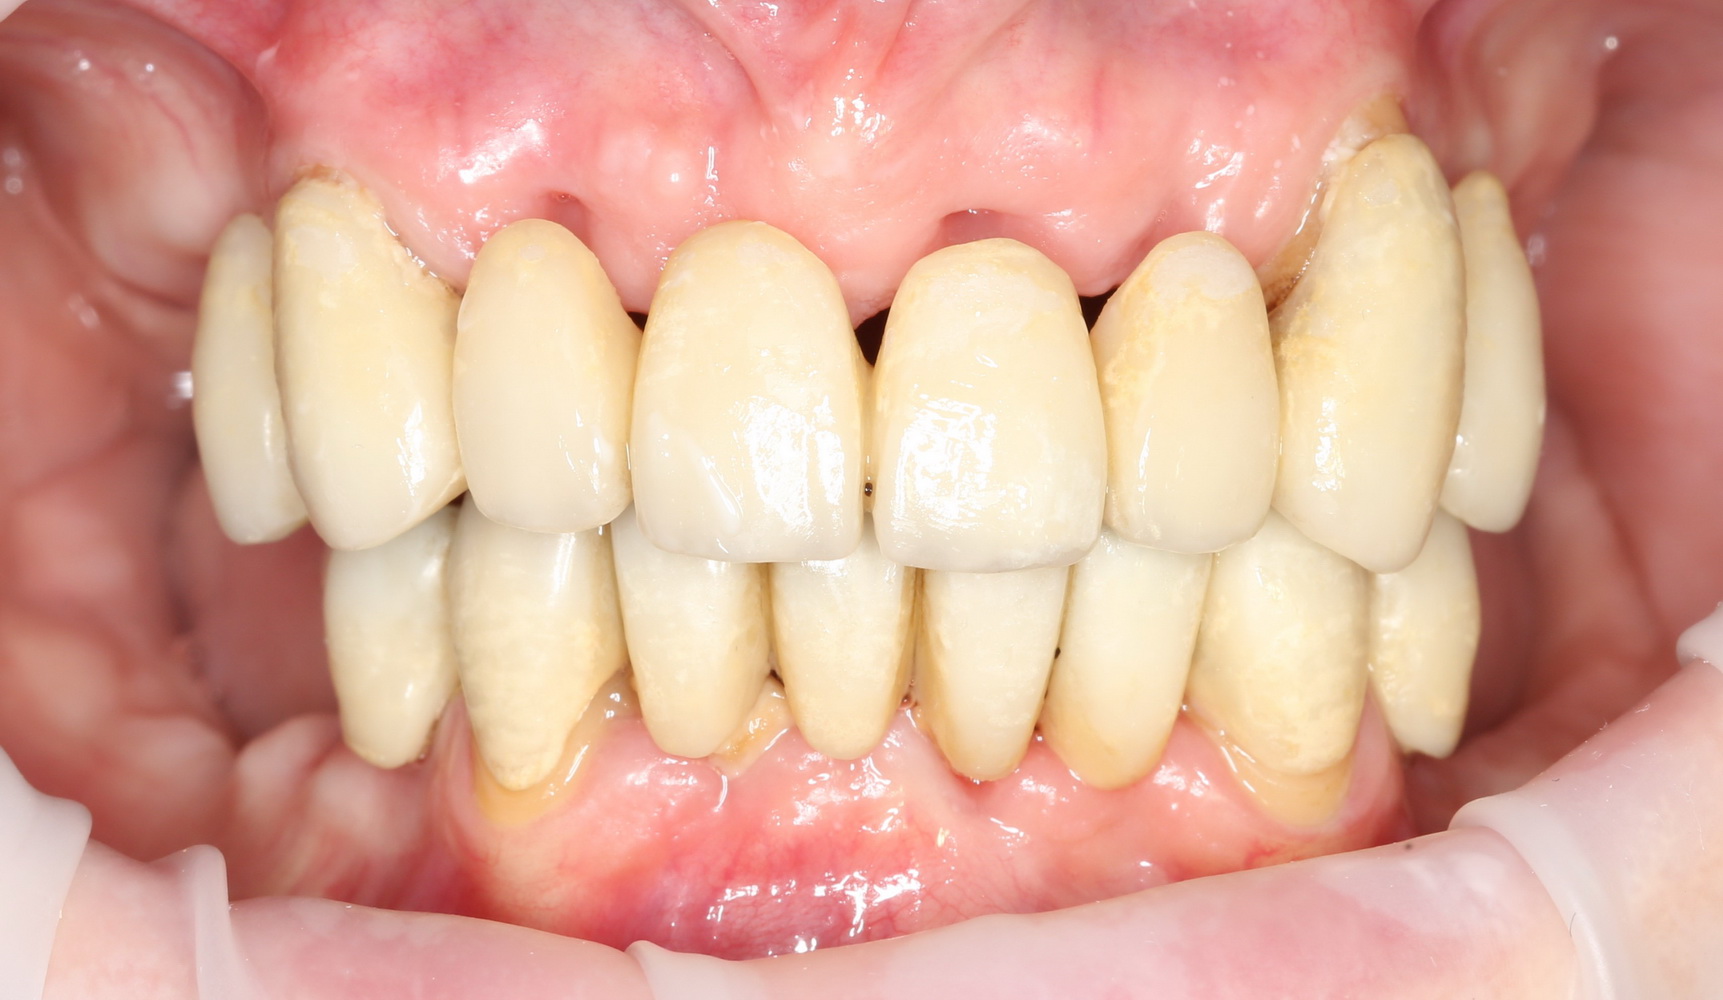

Поэтому мы с Давидом придумали следующее. Мы не стали удалять все зубы, оставили четыре клыка. Это самые большие зубы нашего организма, способные выдерживать значительную нагрузку. Эти четыре клыка Давид использовал как опору временного несъемного (!) протеза, состоящего из восьми (!) единиц на каждой челюсти:

на фотографии вы видите состояние этого протеза, примерно через полгода после начала лечения.